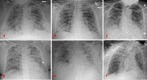

Results: Three thousand three hundred sixty-eight patients were admitted to our institution between March 1st, 2020 and June 8th, 2020 for suspected COVID 19 pneumonia, 902 patients were nasopharyngeal swab positive. Six cases of COVID-19 patients who developed spontaneous pneumothorax were identified (0.66%). Their baseline imaging showed diffuse bilateral ground-glass opacities and consolidations, mostly in the posterior and peripheral lung regions. 4/6 cases were associated with mechanical ventilation. All patients required placement of a chest tube. In all cases, mortality (66.6%) was not directly related to the pneumothorax.